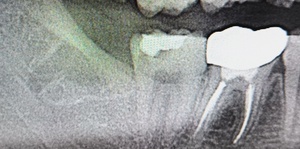

Before(下親知らずの抜歯前) 横に生えた状態で埋まっている親知らず 虫歯がある親知らず 抜歯前の骨の状態のレントゲン像

原因をより詳しく調べるためレントゲンを撮影したところ、右下の親知らずは骨の中に埋まった状態のまま真横に生えて隣接する歯を押しており、前方の歯が虫歯になっています。 そのため、右下の親知らずと隣の奥歯の間には、歯と歯ぐきの境目の溝である「歯周ポケット」が通常よりもかなり深くなっていました。

以上の点から、痛みの原因は深くなった歯周ポケットの中で歯垢が溜まって細菌が繁殖し、親知らず周囲の歯ぐきに炎症が起きる「智歯周囲炎」であると診断しました。